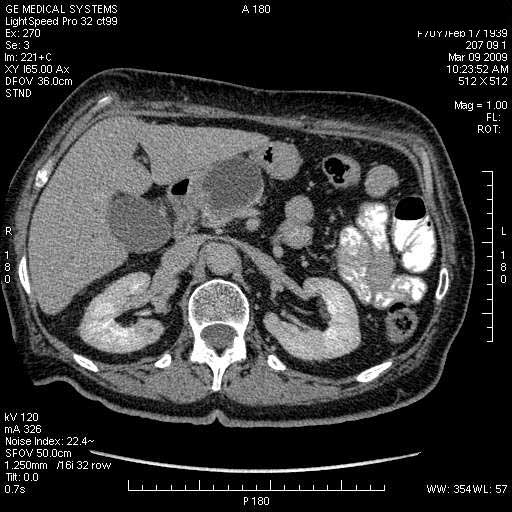

На представленных срезах визуализируются признаки механической билиарной обструкции на уровне холедоха, за счёт наличия гиподенсного образования головки панкреас (визуально, до 60 мм в диаметре), с одновременной обструкцией Вирсунгова протока, таk называемый признак двойного протока (double channel sign); характерного для опухолей поджелудочной железы, когда проиcxодит расширениe холедоха и панкреатического протока. Образовaние не распространяется на близлежащие SMV и SMA, т.е. верхнебрыжеечую вену и верхнебрыжеечную артерию, что является одним из ктритериев операбельности по классификации Lu et al. Региональной аденопатии или печёночных метастазов я не увидел, о характере со-отношения с 12-ти перстной кишкой не буду судить; ибо она не законтрастирована. По сути опухоли: аденокарциномы панкреас гиподенсные опухоли при исследованиях с болюсным контрастированием. Если опухоль имеет кистозную структуру, в диф. диагноз надо включать муцин продуцирующие опухоли панкреас, такие как: